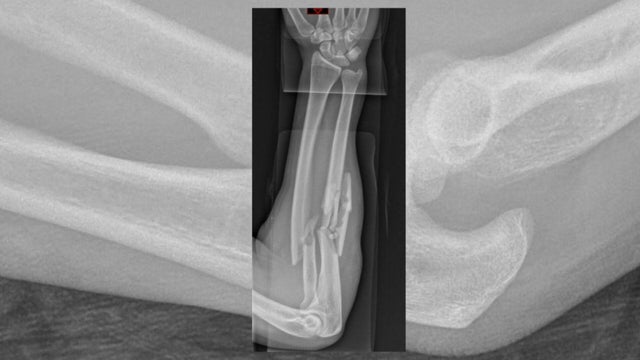

"We started having patients come in with fractures, and some pretty bad fractures too," Lauder said.

The first year study period saw about 200 patients with e-scooter injuries of which half required surgery. Lauder added that care often costs thousands of dollars for e-scooter related injuries.